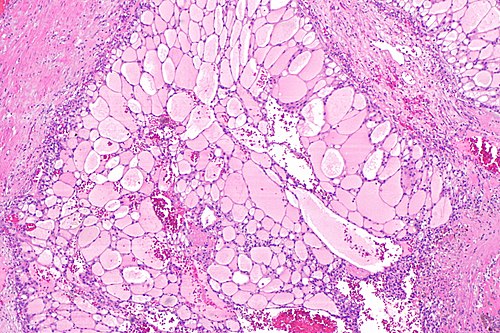

Clear cell renal cell carcinoma -- intermed mag.jpg

Clear cell renal cell carcinoma